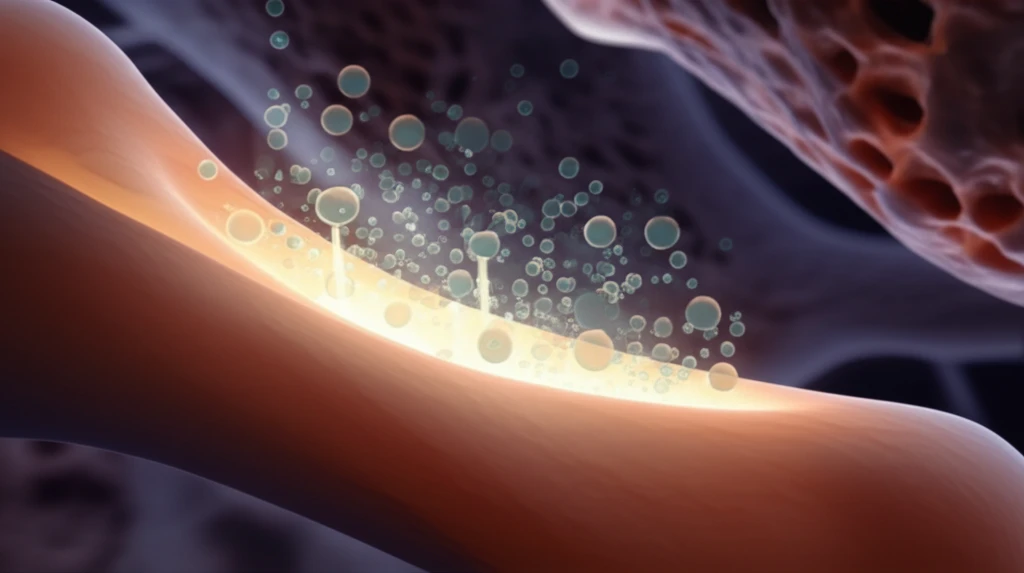

Now, a new study offers a promising solution: enhancing bone cement with calcium phosphate spheres. These tiny spheres can be loaded with antibiotics and strontium, a mineral that promotes bone growth. The goal is to create a bone cement that not only fights infection but also improves the integration of the implant with the surrounding bone.

The researchers incorporated strontium-doped calcium phosphate spheres (SCPS) into the bone cement. These spheres act like miniature drug reservoirs, slowly releasing antibiotics over time. To test the effectiveness of this approach, they compared the antibiotic release of bone cement with and without SCPS.